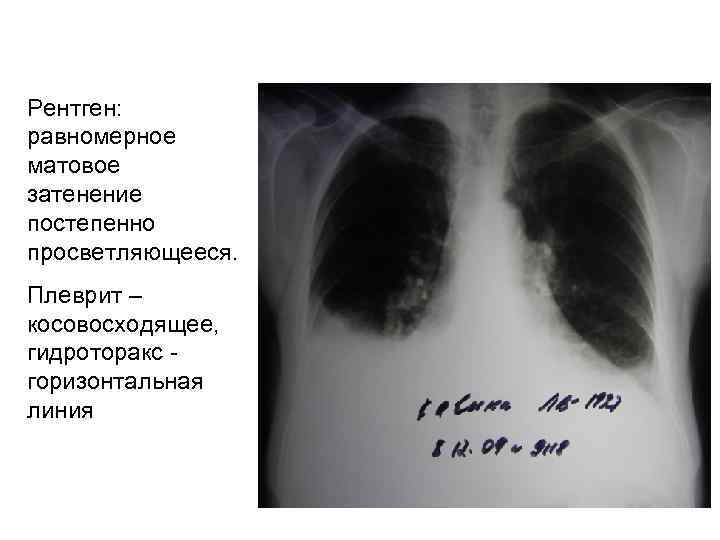

Рентген: равномерное матовое затенение постепенно просветляющееся. Плеврит – косовосходящее, гидроторакс горизонтальная линия